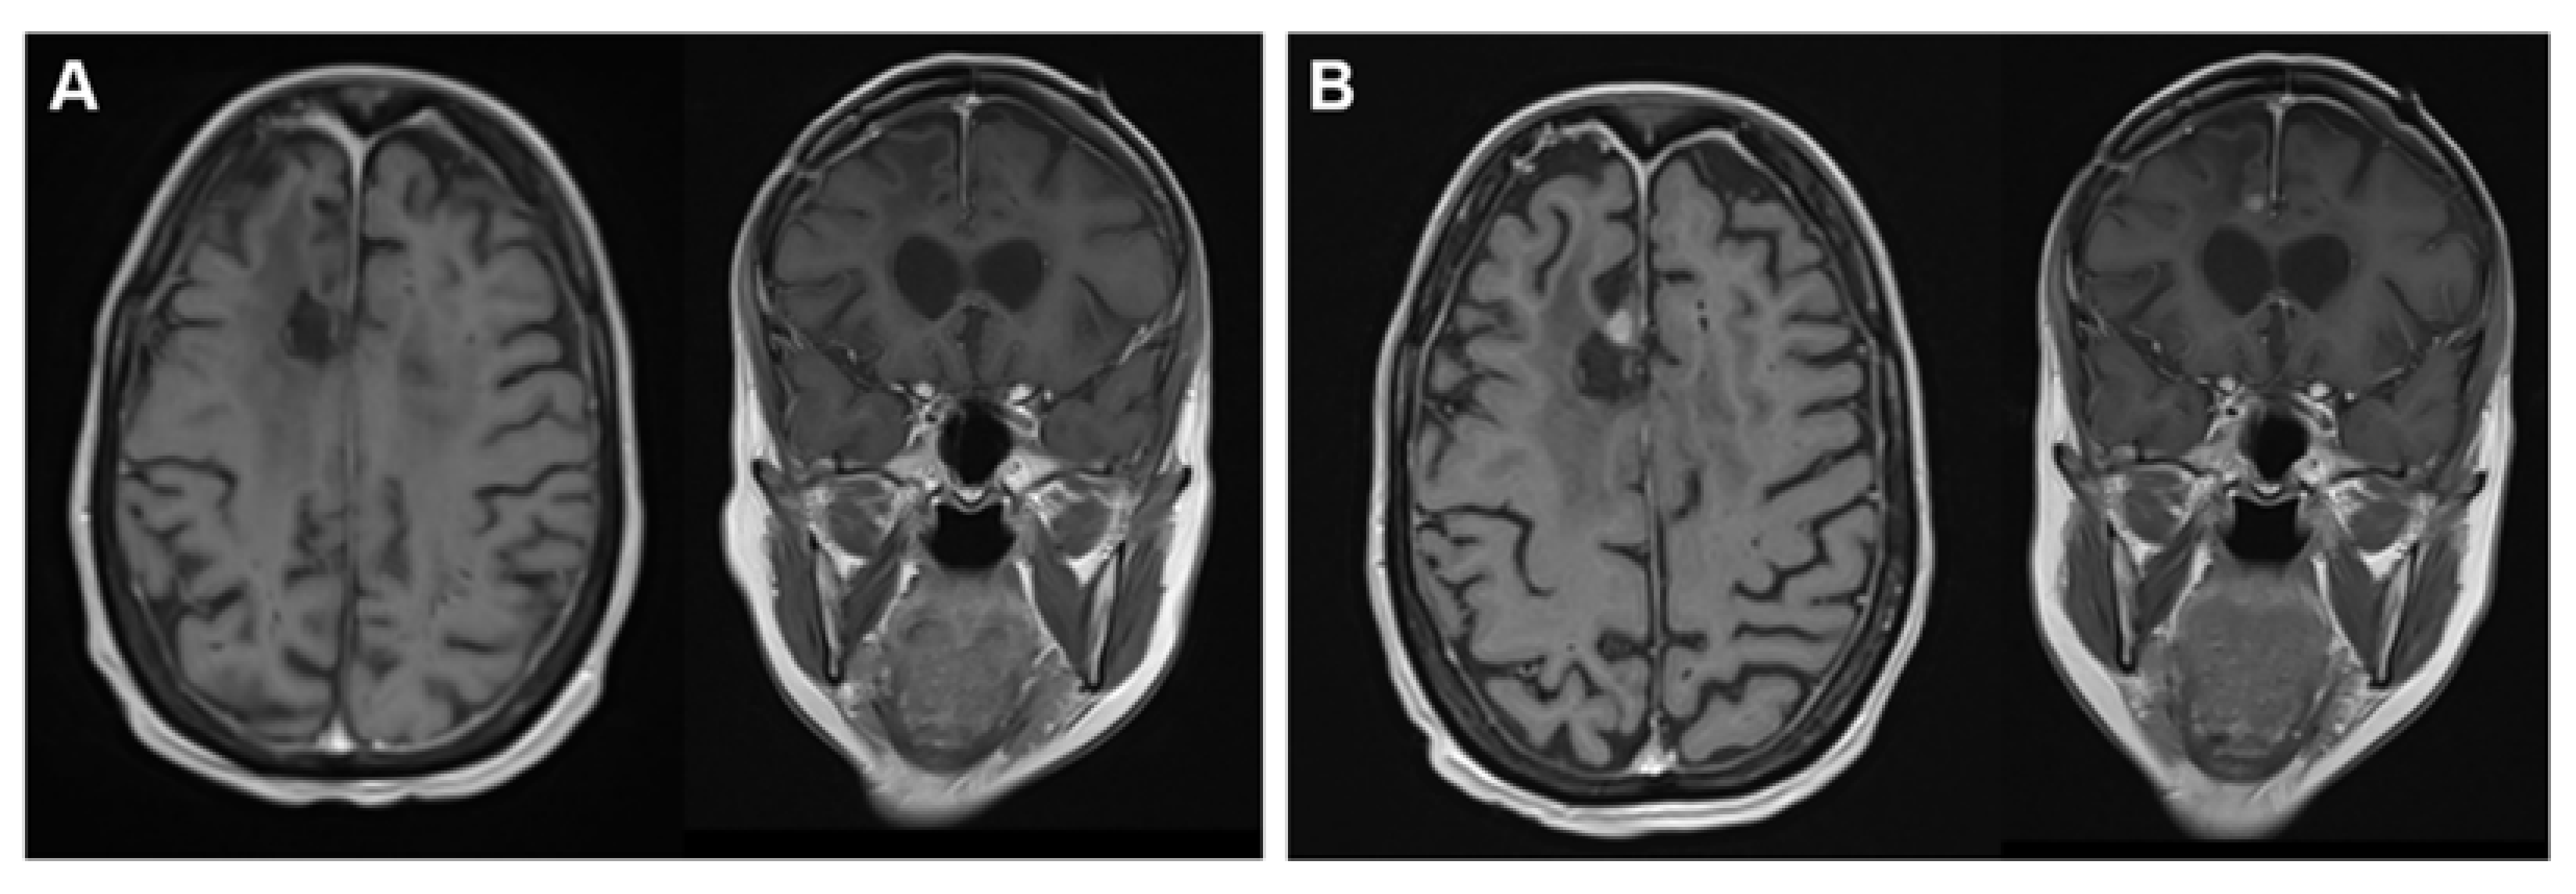

2. Case Report